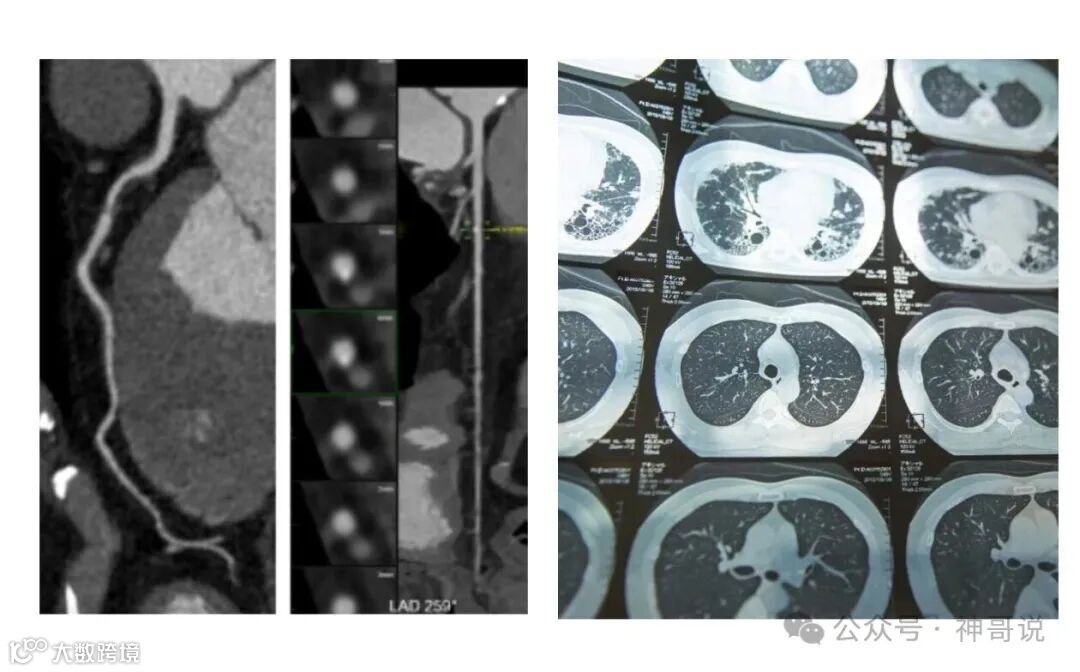

二、放射类检查:放宽部位限制,遵循临床需要

重大调整:CT、磁共振等大型检查的部位数量限制大幅放宽,更加贴合临床实际需求。

1. CT检查

CT平扫:超过三个部位不再受限,按实际检查部位收费。

CT增强扫描:超过三个部位不再受限。

CTA(血管成像)和CT平扫现在可以同时收费。

CT灌注成像与同一脏器的CT平扫不得重复收费。